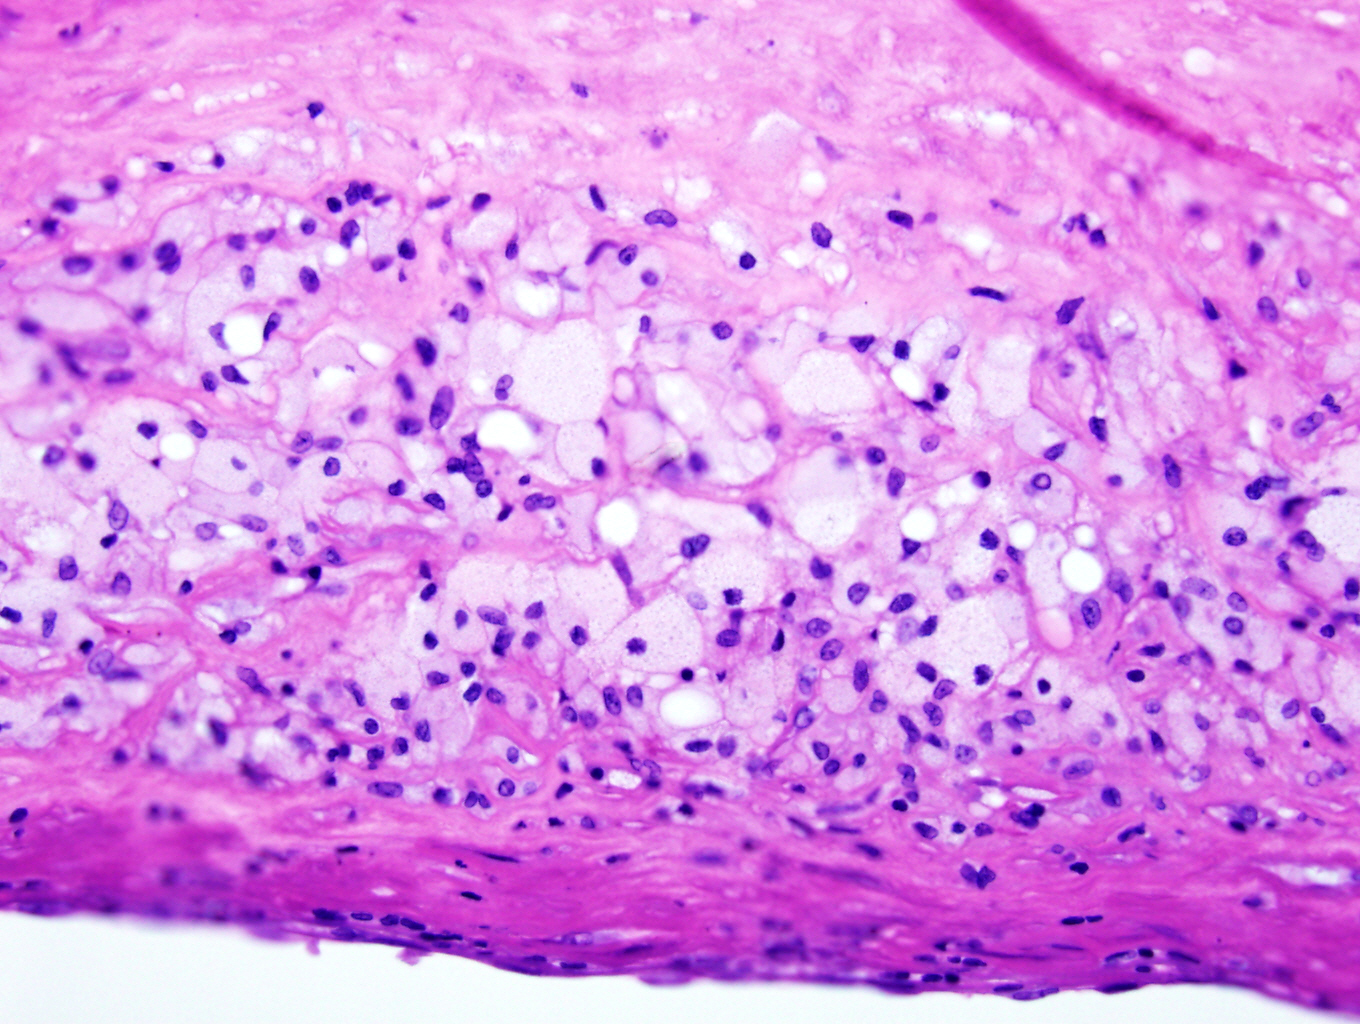

Microscopic (histologic) description

- Fatty streak: subendothelial accumulation of foam cells without necrotic core or fibrous cap

- Fibrous cap atheroma (Am J Med 2009;122:S3):

- Well formed necrotic core with overlying fibrous cap; smooth muscle cells, macrophages, lymphocytes and connective tissue components may be present

- Fibrocalcific plaque: collagen rich plaque, contains large areas of calcification with few inflammatory cells, necrotic core may be present

Microscopic (histologic) images